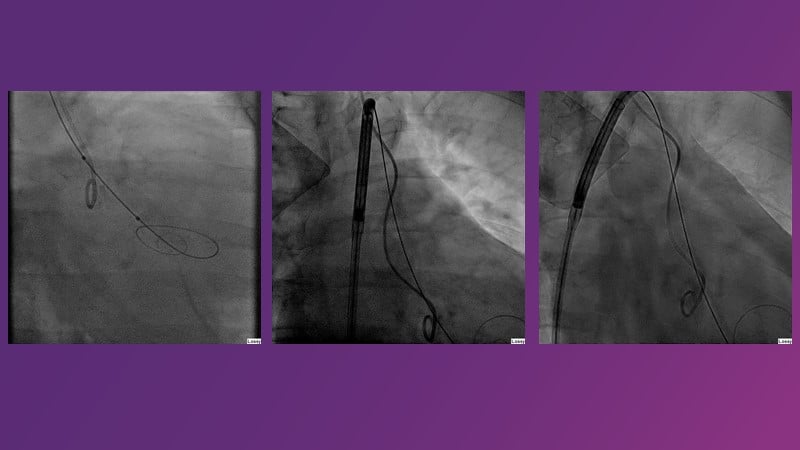

This session reflects on the importance of device choice and implantation technique in complex TAVI procedures. Learn how to anticipate the risks of a valve-in-valve procedure in small surgical prostheses, and discover the latest technological evolutions for treating patients with complex anatomy.